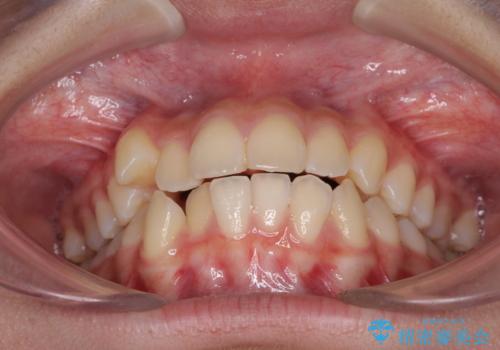

- 前歯のデコボコと八重歯を気にして来院された患者様です。

本人はあまり実感はありませんでしたが、同席されたご家族より口がすぐに開いてしまうことを指摘されていました。

口元に力の入る歯列であったため、上顎左右第一小臼歯4本を抜歯するワイヤー矯正を行うこととしました。

当初は八重歯やデコボコが一番気になっていましたが、抜歯矯正により口元の突出感が改善されるにつれ、口の閉じやすさを実感するようになってきました。